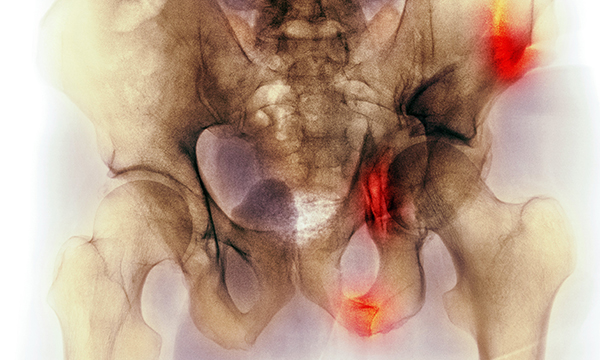

Older people have an increased risk of dying in the first eight months after a pelvic fracture, new study results suggest.